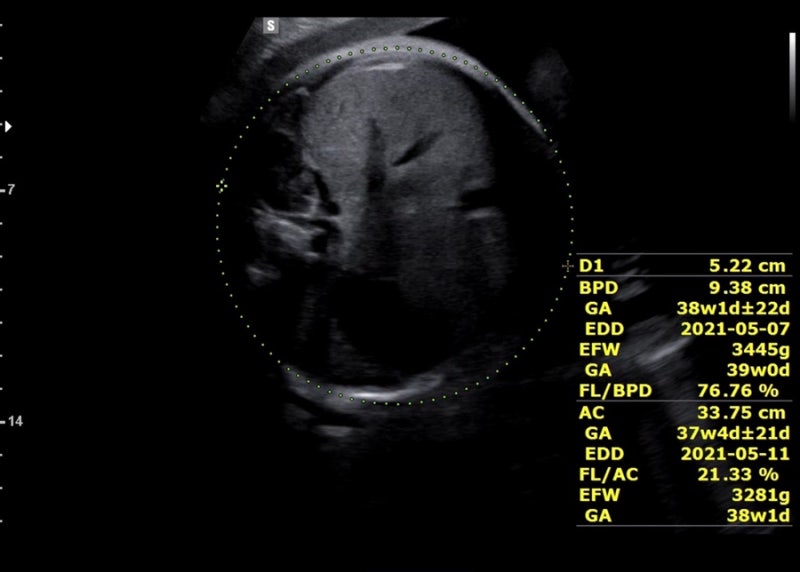

지금은 36주부터 출산까지 매주 목요일 병원에 가서 NST를 통해 태아의 움직임과 심박수, 자궁수축을 기록해 태아가 잘 있는지 확인하고 있다.

![]()

엄마가 음식(특히 단것)을 먹으면 움직임을 측정하기 쉽다고 한다. 기계 도면으로 인해 태아는 아침보다 밤에 더 활동적이어서 검사 중에는 움직임을 많이 잡지 못했으나 여전히 정상 범위 내이며 심박수는 130~130 사이에서 관찰하기 쉽습니다. 170. 1차 검사에서 큰 1개, 작은 3~4개 적발돼 정상이었다. 분만 시 자궁수축이 더 잦아진다고 하는데, 분만 브이로그를 보면 분만 당일 강도가 100을 넘는 게 규칙적이다. B-초음파는 양수의 양과 태아의 위치를 확인하기 위해 매주 할 수 있는 것 같고, 양막의 크기는 큰 것 하나, 정상인 것 하나 총 두 번 측정했다. 응! ! ! ! ! ! ! ! ! 긴 의료 설명, 의사가 마지막에 추가했습니다. 정상, 괜찮습니다. 동양인 엄마의 체형(골반), 아기의 머리둘레, 회음부절개에 대해 물어봤습니다. 미국에서는 관장, 제모, 외음절개술을 시행하지 않는 것으로 알려져 있지만 외음절개술이라면 의학적으로 필요하거나 필요하다고 합니다. 머리둘레 걱정했는데 제왕절개까지 고려하기엔 역부족이었고(조건은 자연분만일 수 없음: 아기의 몸무게는 5kg임), 산도에서 나오면 아기의 머리 모양이 질 입구에 딱 맞으니 걱정하지 마세요. 걱정되는 저를 안심시키기 위해 의사선생님께서 의료진이 최선을 다해 도와드리겠다고 말씀해주셨습니다. 저도 오늘 B초음파를 하는 이유가 궁금했는데 그게 아니라서 모른다고 하더군요. 이유. 미국의 대답. 오늘 만난 의사는 최근 이상한 변호사 Wu Yingyu를 보는 것을 즐겼다고 말했습니다. 그래서 치료받는 내내 웃음을 참을 수 없었습니다. 덕분에 불안한 마음이 많이 진정되었어요~ 산모가방 싸기 파워J형 K형 산모가방 미국 병원에 있어요~ 정상분만 1박2일만에 퇴원하고 3일만에 그리고 제왕절개 2박.. 한국처럼 큰소리로 산부인과 가방을 싸갈 필요도 없고, 준비물은 다 구비되어 있다고 해서 퇴원할 때 아기옷, 잠옷, 기타 등등 챙겨가셔야 합니다. 산모에게 안정적인 담요를 제공할 수 있는 것. 필요없으시면 다시 가져가시면 됩니다. 필요하지만 그것 없이는 살 수 없습니다. 그래서 제가 챙겨가는 것은 여권, 보험증, 속옷(수유브라), 수면양말, 겉옷, 면속옷, 수유패드, 수유패드, 가슴확대키트, 유축기, 유두보호대, 손목싸개, 회음부패드, 비데, 영양제, 임부복(산모안전속옷), 생리대(1박), 세면도구, 구강청결제, 립밤, 헤어밴드, 기초화장품, 스트레치마크크림, 실내슬리퍼, 휴대폰충전기, 보조배터리, 마스크, 알약, 간식 /다과, 카시트, 포대기, 핸드백, 포장지(담요), 거즈손수건, 젖병, 겉옷(바디슈트), 아기모자, 물티슈, 비타민D, 유산균* 출생신고가 필요하여 퇴원 전 아기의 이름을 정했습니다. 아기의 이름은 최종 후보 2명까지 고려 중이지만, 생년월일과 시간을 보고 최종 결정하게 된다. 산부인과/산부인과/학과 전문용어 외우기 언어차이 극복 미국에서 출산이라는 번거로운 일을 앞두고 가장 걱정되는 것이 언어와 문화차이인 것 같아요. 언어차이는 있지만 통역사들이 있긴 한데… 통역사들의 질이 별로 좋지 않고, 케이블에 제약이 있어서 아기가 생기면 통역사를 안 쓸 생각입니다. 생명이 위급한 상황에서 자신을 보호하기 위해 관련 용어를 숙지합니다. 조산전 산부인과 산부인과 GYN 산부인과 소아과 소아과 둔위전위 태반 미숙아/미숙아 양수 양막 양막 양막 SROM(자발성 막 파열) 파열, 양막 파열 태반 태반 임신 전 당뇨 거림메스꺼움 데데이트, EDD(예상분만일), 자연분만, 자연분만, 제왕절개, 제왕절개, 태아태아, 지진마사지, 막스윕입원, 병원 둘라 / 자간전증이 있는 임산부(증상: 단백뇨, 두통, 부종 등) 저혈압, 저혈압(체외수정) 비스트레스 검사(NST) 경험, 임산부가 편안하게 눕힌 후 20분 동안 산모의 복벽에 모니터를 설치하여 태아 심박수 모니터링 파악 태아의 건강 상태 분만(시간), 분만(과정) 분만, 분만 분만 수축 분만 수축 실제 분만 수축은 점액 마개를 드러내고, 혈액은 자궁 수축을 보여줍니다. 미국 선택, 필요한 경우 37-8주부터 시작) 자궁경부 검사, 내부 검사 내가 확장되고 있는지 확인할 수 있습니까? 확장(자궁문이 열림을 나타냄/0-10cm) 무통 경막외 마취 주사 태아 운동 분만 유도, 분만 유도 흑선 외음절개 회음부(또는 질) 열상(또는 열상) 1도 열상: 1도- 2도 열상(피부 및 피하 조직에 한하며 심한 출혈을 일으킬 수 있는 요도주위 열상 포함) – 2도 열상: 2도 열상(질 괄약근의 근막 및 근육층에 나타나며 항문 괄약근은 영향을 받지 않음) – 3도 열상 열상: 3도 열상(항문 괄약근 및 직장질 횡격막에 영향을 미침) -4도 열상: 4도 열상 상부(항문 및 직장 점막에 영양 공급, 이때 완전히 치료하지 않으면 직장질 누공으로 이어질 수 있음) 관장 산도 탯줄, 탯줄 겸자 산파, 겸자 조산 진공 펌핑 회전(알코올) 버전 정맥주사, 정맥주사 담당의사가 담당의사 대기 중 의사가 퇴원하여 신생아 집중치료실 NICU가 저림 및 출혈 산후출혈 산후 통증 초유, 분유 전 황색 산후 2~3일 묽은 분비물 모유 수유 중 태변 황달/황달 모유 수유 금이 간 유두 황달, 수유 중 또는 수유 사이에 지속적인 유두 통증, 유방 충혈, 분만 후 유방 통증 또는 전신 모유 수유 염증, 유방 통증 유륜 건선 Fluff Lanugo Sitz B형 간염 연고 가임력 산모 피임약 GBS Bacterial Check (37주 + 5회) Group B Streptococcus Bacterial Check 임산부의 질이나 직장에 상주하는 GBS(Streptococcus B)는 신생아 패혈증 및 수막염의 주요 원인 . 신생아가 GBS에 감염되면 일부는 사망하고 생존하더라도 합병증이 발생해 후유증을 동반할 수 있다. GBS는 임산부의 생식기나 위장관에 특별한 증상이 없지만 자궁이나 출산 중 감염을 일으킬 수 있습니다. 따라서 35~37일 말에 GBS 검사에서 양성 반응을 얻으면 분만 내내 항생제나 조치를 취해야 한다. 흔한 세균이고 산모 4-5명 중 1명이 양성 반응을 보여서 크게 걱정하지는 않지만 음성 반응이 나오기를 바라고 있습니다. 개별 포장된 의료용 면봉으로 질입구 -> 직장입구 순으로 5~7회 이상 닦은 후 면봉봉을 절취선에 따라 부러뜨린 후 용기에 삽입합니다. 1~2분 정도 소요되며 매우 간단합니다. 코로나 자가진단키트 느낌. 결과는 며칠 이내에 앱을 통해 받을 수 있습니다. 지난달 메디신볼 운동으로 골반이 활짝 열렸으니 계속 해보세요! 도움을 받을 수 없는 상황이기 때문입니다. 그래서 37주차에 들어가면서 하루에 30분씩 런닝머신 + 엑서사이즈 볼을 하고 있습니다. 내 골반이 부드러워졌으면 좋겠다. . . 집에서 운동을 많이 하지는 않는데 이 영상은 15분짜리입니다. 시간가는 줄 모르고 그냥 따라갔어요. 남편과 소중한 시간을 보내세요. 한동안 우리 집에서 조용한 시간은 없을 텐데(feat. 칼리 날씨) 이제 부모님 오실 날도 일주일 앞으로 다가왔습니다. 그들은 친밀한 시간을 보내고 있습니다. 육아에 직격탄을 맞으면 임시 연애는 어려울 수 있다. 결혼 후 3년간의 격렬한 놀이, 술, 여행. 그들은 신혼부부로서 할 수 있는 모든 일에 자부심을 가지고 있습니다. 슬프다, 이상하다고 생각한다. 캘리포니아의 날씨는 요즘 늦봄(15~20도) 같아서 공원에 가서 샌드위치+커피를 먹기도 좋고, 교외를 드라이브하며 맛집을 찾아 다니기도 좋고… 마지막인 것 같아서 더 재밌어요 ㅎㅎ 밖에 나가야 할 정도로 먼 길을 갈 수는 없었지만, 가까이 있다는 소소한 행복이 출산의 설렘을 달랬습니다. 부모님이 오신 후에도 우리 가족은 적어도 일주일 동안 외식을 하고 당일치기 여행을 할 수 있었습니다. 원하다… !